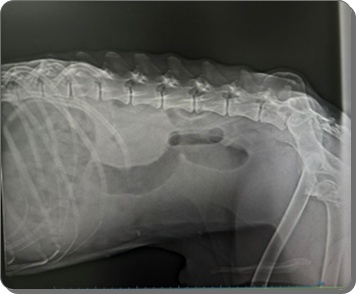

Der Abdomen erscheint ebenfalls mit Flüssigkeit gefüllt, sodass der Verdacht

auf eine kardiale Problematik geäußert wurde.

In der Röntgenuntersuchung der Gliedmaßen wurden Veränderungen festgestellt,

die auf eine beginnende Osteoporose hinweisen, sodass die Knochenstruktur

als nicht gesund bewertet wird und eine erhöhte Fragilität

(leichteres Brechen) anzunehmen ist.